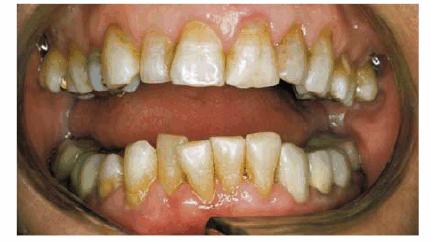

Figures 29-6A, 29-6B, 29-6C, 29-6D, and 29-6E illustrate a patient who did not care much about his

smile. The motivation for pursuing esthetic dentistry was his wife. She thought

that his smile made him look much older than his years. She encouraged him to

have esthetic dentistry by telling him that she would not kiss him until he had

his smile improved. Figures 29-6A, and 29-6D show the worn and discolored central incisors and the

crowded lower anterior incisors. Figure 29-6B shows cosmetic contouring of the lower incisors.

Figures 29-6C, and 29-6E illustrate the completed esthetic improvement following

composite resin bonding of the central incisors.

Figure 29-6A: This 65-year-old man displayed worn, discolored maxillary central incisors with a fractured anterior composite restoration on tooth #9.

Figure 29-6B: Cosmetic contouring of mandibular incisors.

Figure 29-6C: The view after composite resin bonding of his central maxillary incisors.

Figure 29-6D: This man avoided smiling to hide his worn, discolored, and fractured central incisors.

Figure 29-6E: Note how much younger and happier the patient is following his esthetic dental treatment.